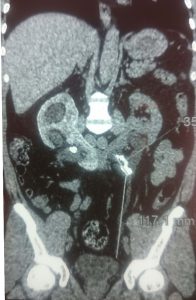

Phẫu thuật lấy sỏi thận trên bệnh nhân bị thận móng ngựa

Ngày 07/8/2017, kíp phẫu thuật khoa Ngoại thận – Tiết niệu, Bệnh viện Đa khoa [...]